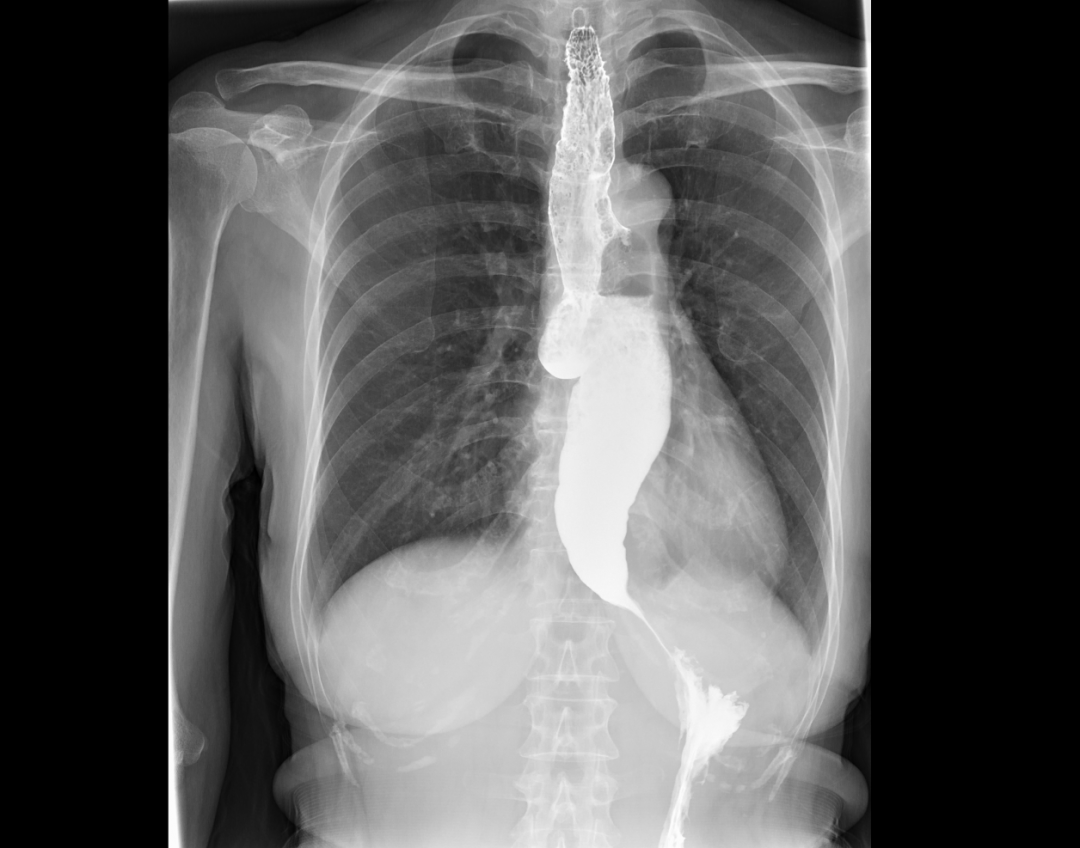

住院后医生为她安排了胃镜检查和上消化道钡剂造影,检查结果提示贲门失弛缓及食管中段憩室。

韩梅病情特殊,消化内科主任李滨教授和副主任肖绪华在详细阅读各项检查报告后,发现患者食管下端呈“鸟嘴样”改变,同时上端分别紧接一个约2.5cm大小的憩室,结合患者病史,明确患者“贲门失弛缓合并食管中段憩室”的诊断。他们认为造成了韩梅多年梗噎和反流的病的原因是:食管下段肌群持续紧缩,蓄积的食物被迫推向多发的憩室,加重憩室的扩张,食管及憩室内食物反流。

造影图(食管下段“鸟嘴样”改变,食管中段憩室